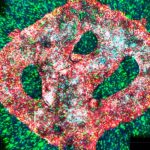

Tumor cerebral maligno impreso en 3D (VIDEO)

Un equipo de científicos israelíes ha conseguido imprimir con éxito el primer tumor cerebral maligno activo del mundo impreso 3D, siendo hasta el momento...